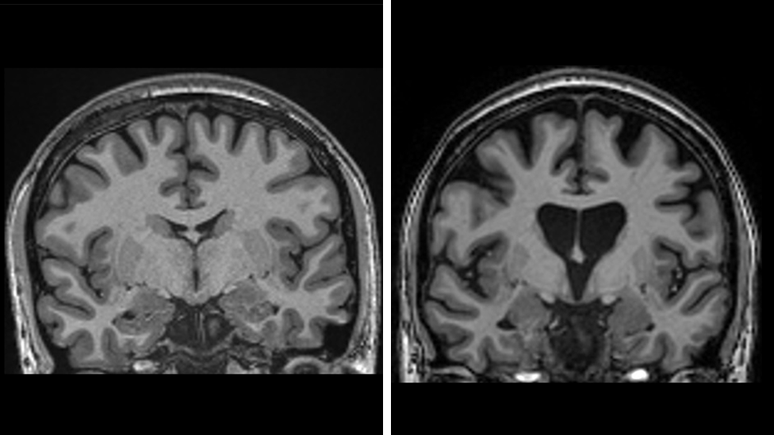

A imagem à esquerda mostra um cérebro saudável. À direita, vemos a perda de matéria cerebral, devido à morte de neurônios causada pela doença de Huntington.